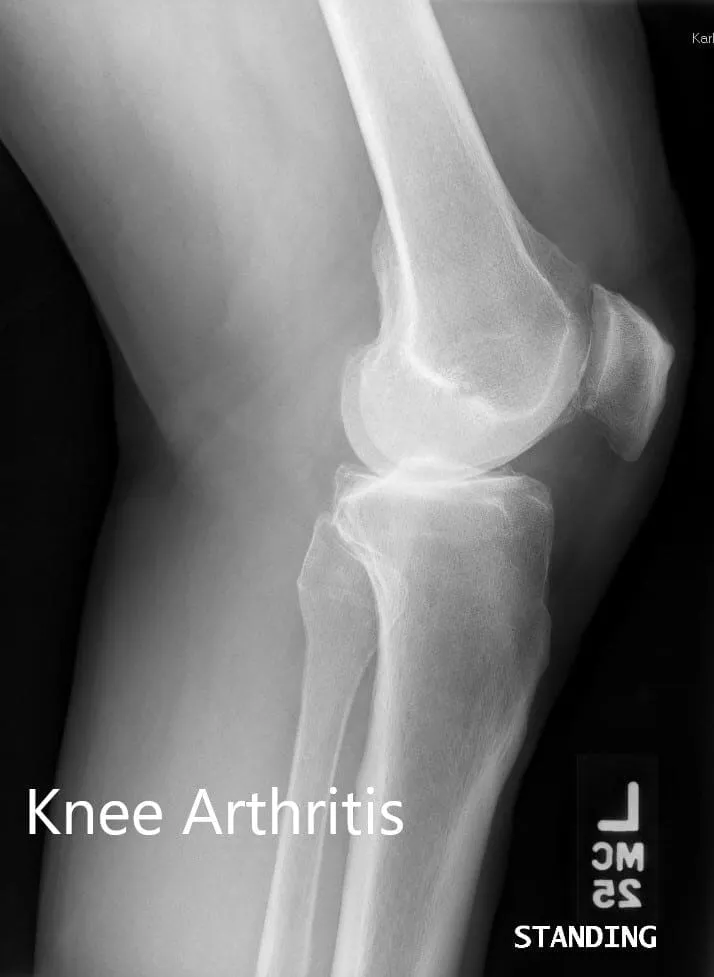

Her imaging studies of both the knee revealed severe tricompartmental osteoarthritis. Considering her lifestyle limiting knee pain, she was advised bilateral custom total knee replacement. Risks, benefits, and alternatives were discussed with the patient at length. She agreed to go ahead with a bilateral custom knee replacement.

Preoperative X-ray showing the lateral views of the right and the left knee respectively.